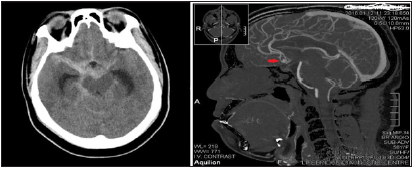

Ethical clearance was sought for and obtained from the three institutions involved in this study namely National Hospital Abuja, Federal Medical Centre Abuja and Wellington Neurosurgical Centre Abuja. Retrospective review of all cases that presented with CT confirmed aneurysmal subarachnoid hemorrhage from Jan 2016 to Jan 2020 was conducted. Those with typical history of SAH, but unable to conduct these investigations were excluded. The Biodata, clinical process (admitting neurology, Grading, CTA findings, Surgical treatment, endovascular treatment, complications of treatment), post op CT/CTA (Figures 1-3) and outcome were reviewed. Data generated were analyzed with simple descriptive statistics and presented accordingly.

Figure 1: Plain CT showing SAH. CTA showing culpable ACOM Aneurysm.

Focal neurological deficits including hemiparesis, optic nerve and oculomotor nerve palsies were also observed. Optic nerve palsy was particularly observed in the case of ophthalmic segment aneurysm due to the close proximity in the optic canal. It manifested as ipsilateral complete blindness. Oculomotor palsy was found in the case of a posterior communicating artery aneurysm due to pressure on the adjacent oculomotor nerve. It manifested as ipsilateral ptosis, mydriasis and impaired extraocular muscles except the lateral rectus and superior oblique. Hemiparesis was due to acute hematoma dissecting into the brain parenchyma from a subarachnoid bleed and manifests as contralateral weakness. In agreement with other studies [10], commonest observed risk factor was systemic hypertension in 66.6% of cases with an average mean arterial blood pressure of 115mmHg, range 83.3- 183, SD-26.9mmHg. The observation also of diabetes, renal disease, and retroviral disease in a few cases were of uncertain link to the SAH. Chronic hypertension is known to cause endothelial injury, occlusion of the vasa vasorum, and disruption of the synthesis of collagen and elastin. These structural changes could initiate a focal weakening in the arterial wall with resultant bulging characteristic of aneurysms especially the saccular type 11. Following initial plain CT revealing a sub arachnoid bleed (Figure 1), all patients had CT angiography which revealed the culpable vessels/aneurysms as detailed in Table 3. In the absence of digital subtraction angiography (‘gold standard’), CT angiography has become the only available tool for investigating and treating neurovascular problems in our environment. In spite of its limitations, many centers have shown good results with CTA detecting up to 97% aneurysms [11,12].